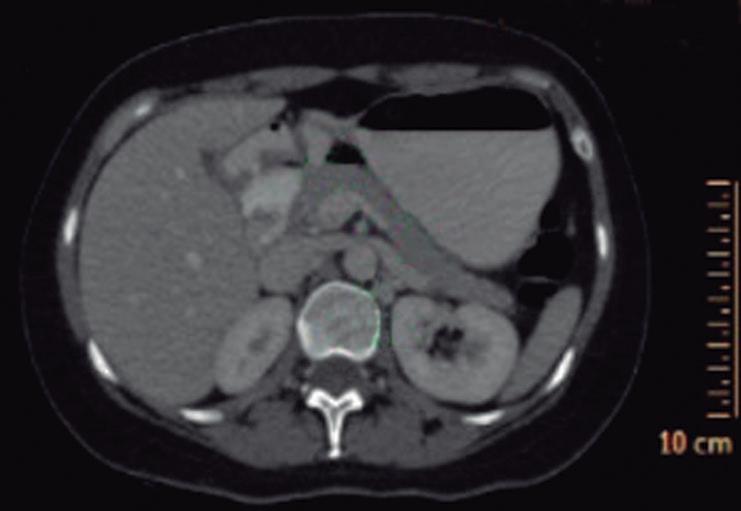

CASOS CLÍNICOS Biopsia guiada por ecoendoscopía como herramienta diagnóstica mínimamente invasiva para metástasis mesorrectal de carcinoma de células claras renales: reporte de caso

Nicole Marie Kahn, Mayra Florencia Defanti, Yanina Gabriela Carlino

CASE REPORTS Endoscopic Ultrasound-Guided Biopsy as a Minimally Invasive Diagnostic Tool for Mesorectal Metastasis From Clear Cell Renal Carcinoma: A Case Report